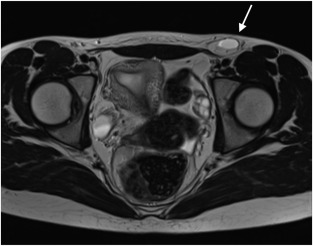

На Т1-взвешенных изображениях определяется грыжевое выпячивание в области бедренного кольца с гипоинтенсивным или изоинтенсивным сигналом в зависимости от содержимого грыжевого мешка.

На Т2-взвешенных изображениях визуализируется гиперинтенсивное содержимое грыжевого мешка, особенно при наличии жидкости или отёка в выпавших структурах.

На изображениях с подавлением сигнала от жира подчёркивается контур грыжевого мешка и наличие перигрыжевого воспаления при ущемлении.

В режиме с подавлением сигнала от воды фиксируется нарушение целостности мышечно-апоневротических структур бедренного канала и отёк окружающих тканей.

В режиме динамического контрастного усиления определяется васкуляризация содержимого грыжевого мешка, что позволяет выявить признаки ишемии или некроза в ущемлённой кишке.

В режиме трёхмерной реконструкции визуализируются размеры грыжевого дефекта, его пространственное соотношение с бедренными сосудами и глубина проникновения грыжи.

- Размеры и форма грыжевого дефекта в бедренном канале.

- Состав содержимого грыжевого мешка с разграничением между сальником, петлями кишки и жидкостью.

- Толщина и структура стенок грыжевого мешка при воспалении или ущемлении.

- Признаки ишемии или некроза ущемлённого органа на основании изменения сигнала и перфузии.

- Состояние окружающих тканей бедренного канала и сосудистых структур.